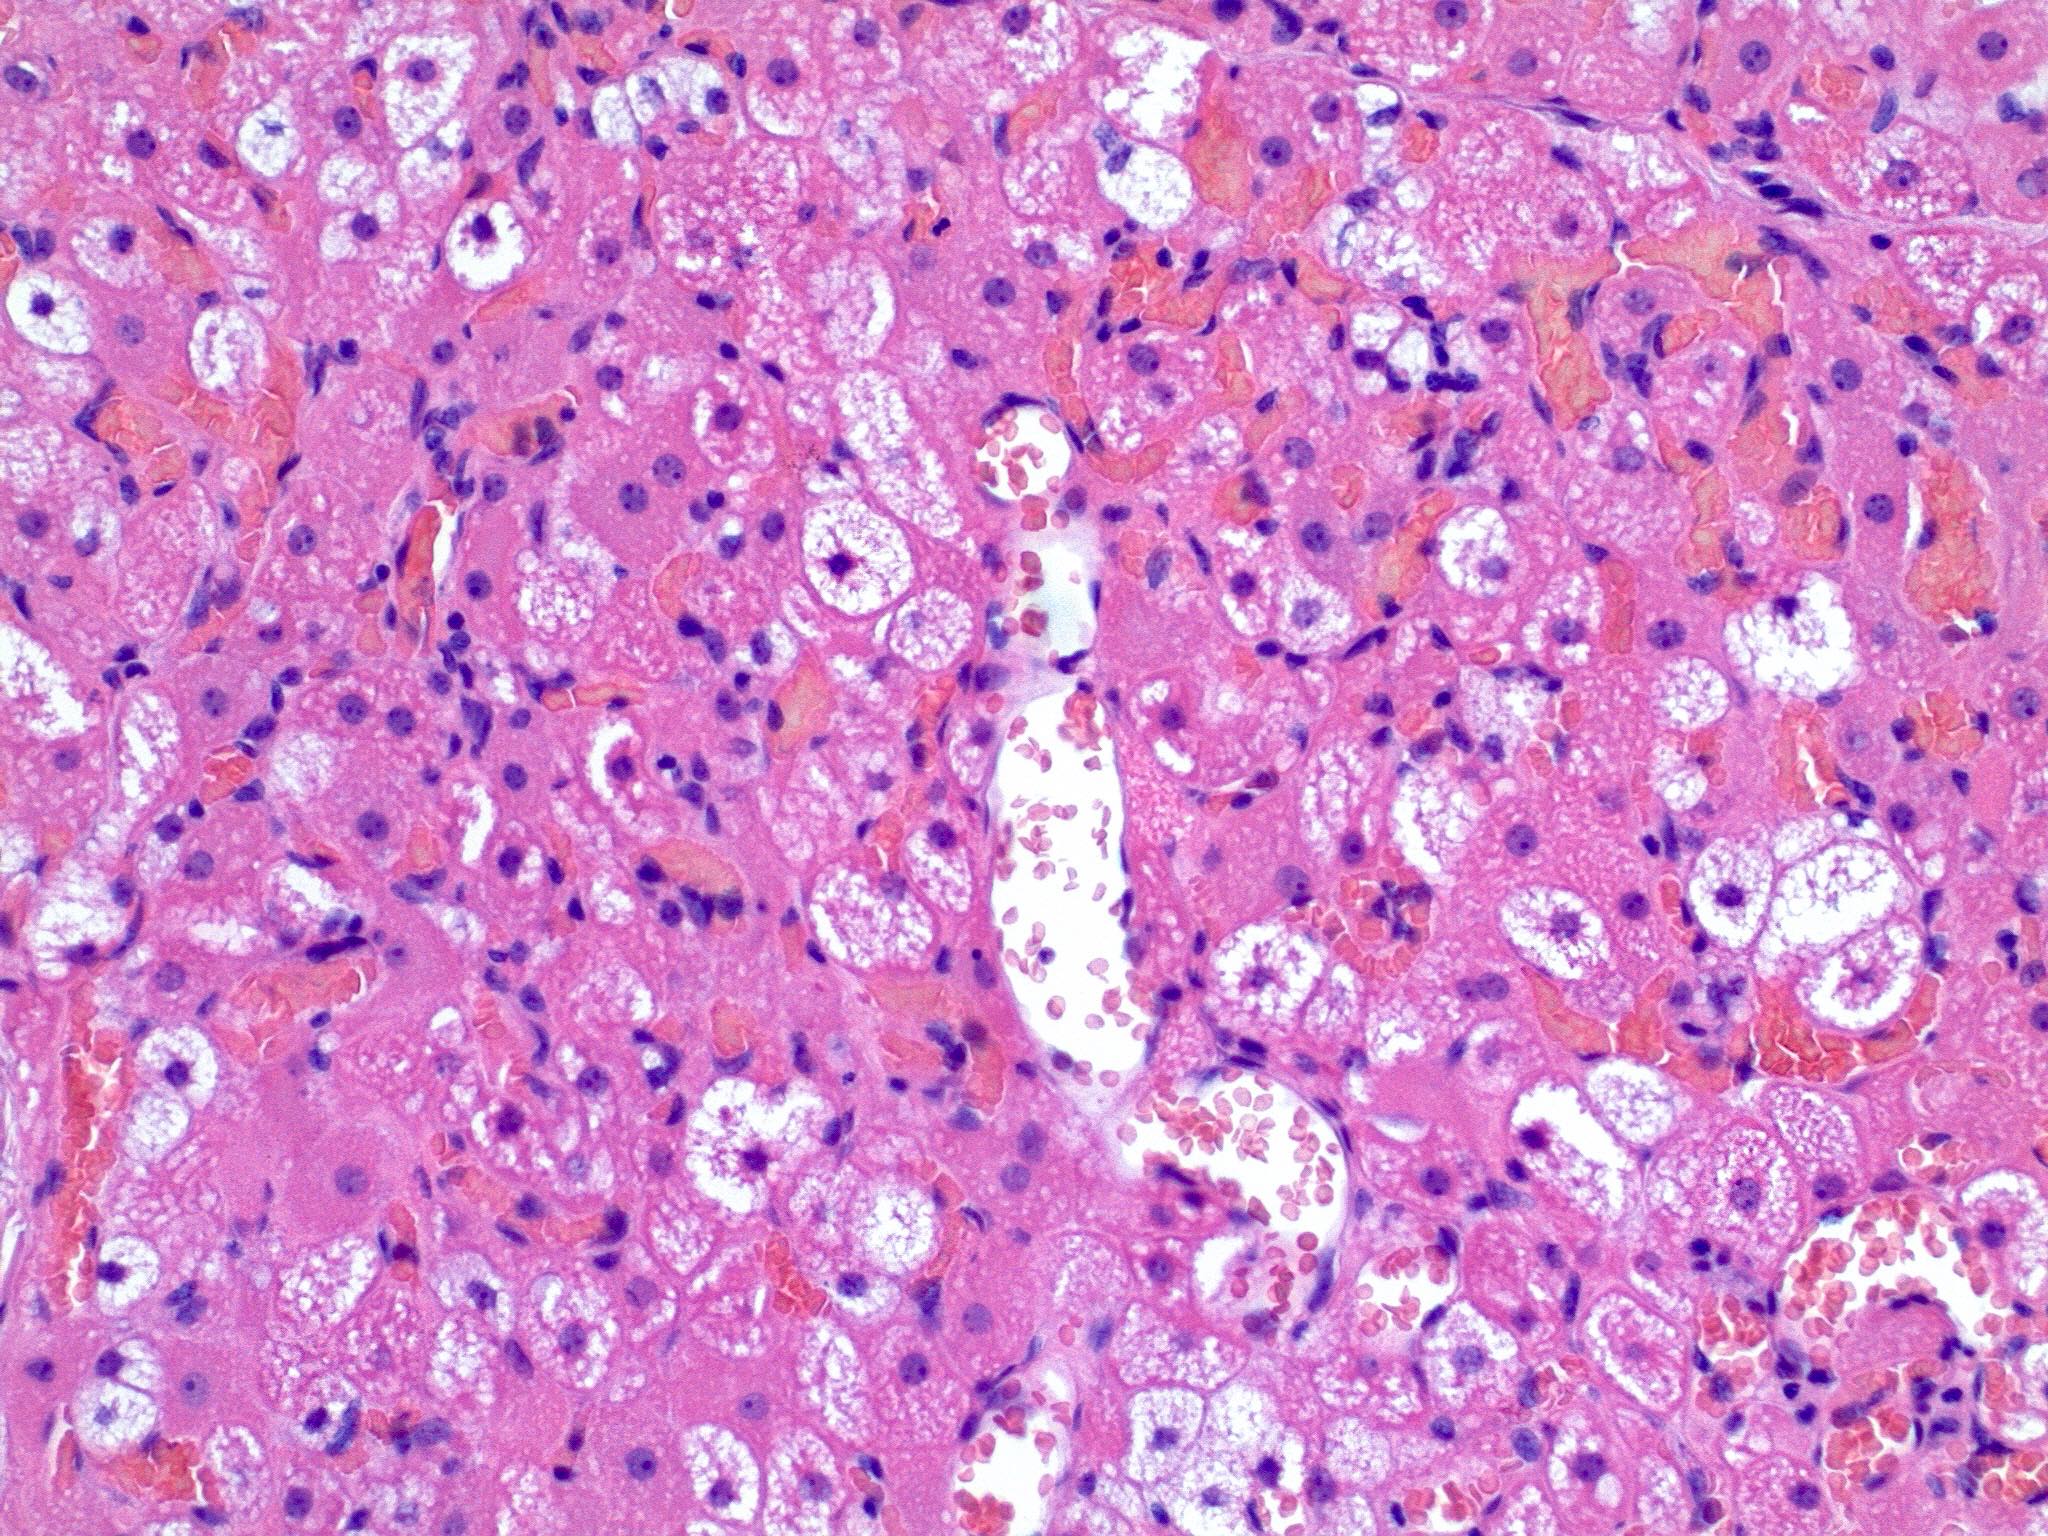

Microscopic (histologic) description

- Neoplastic lesion composed of polygonal brown fat cells with stromal cells in the background (Case Rep Oncol 2017;10:438)

- Large number of pale and eosinophilic brown fat cells with multivacuolated, eosinophilic granular cytoplasm and small central nucleus (about 70%) admixed with variable amount of univacuolated white cells (Case Rep Oncol 2017;10:438, Am J Case Rep 2020;21:e921447, J Comput Assist Tomogr 2019;43:793, J Pathol Transl Med 2017;51:499, Am J Surg Pathol 2018;42:951, Virchows Arch 2021;478:527)

- Multivacuolations resemble lipoblasts

- Morphological variations or subtypes: typical, myxoid (9%), lipoma-like (7%), spindle cell (2%), thick bundles of collagen fibers, presence of mast cells and exclusively containing brown fat cells (Case Rep Oncol 2017;10:438, Am J Case Rep 2020;21:e921447, Virchows Arch 2021;478:527)

- Cytological atypia, necrosis and mitosis is unusual (J Pathol Transl Med 2017;51:499, Am J Surg Pathol 2018;42:951, BMC Surg 2021;21:30)

Microscopic (histologic) images